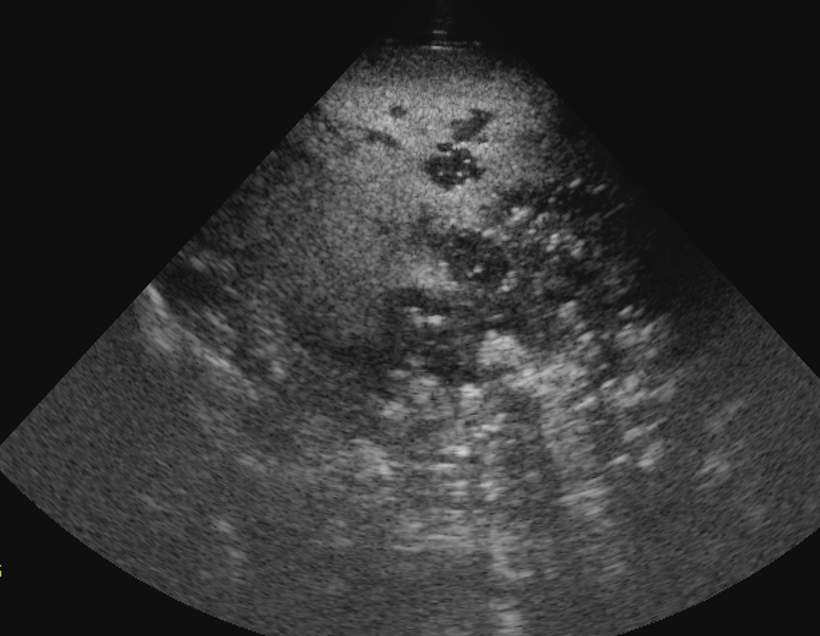

what does this US show?

islands of abnormal tissue in the spleen

can’t see distinct borders of spleen

—> possibly lymphoma